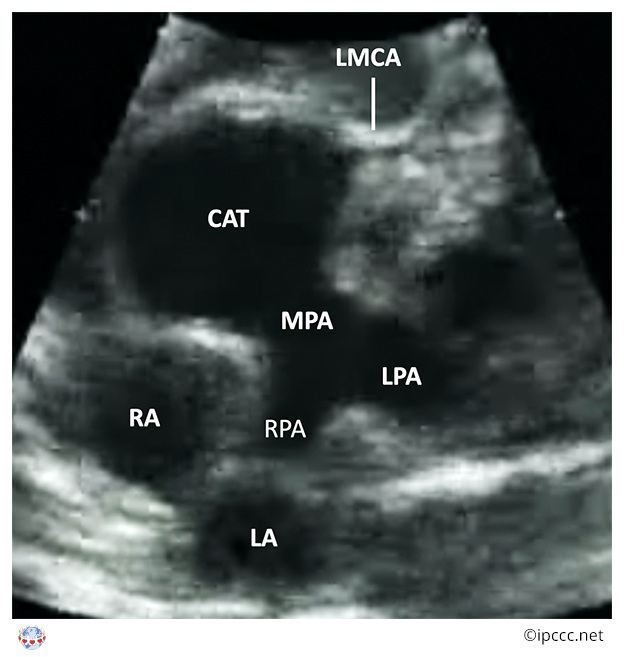

A congenital cardiovascular malformation in which a common arterial trunk is associated with an unobstructed aortic arch and both pulmonary arteries arise from the common arterial trunk.

This category includes Collett and Edwards truncus arteriosus types I, II, III and Van Praagh truncus arteriosus types 1, 2.

Echocardiogram